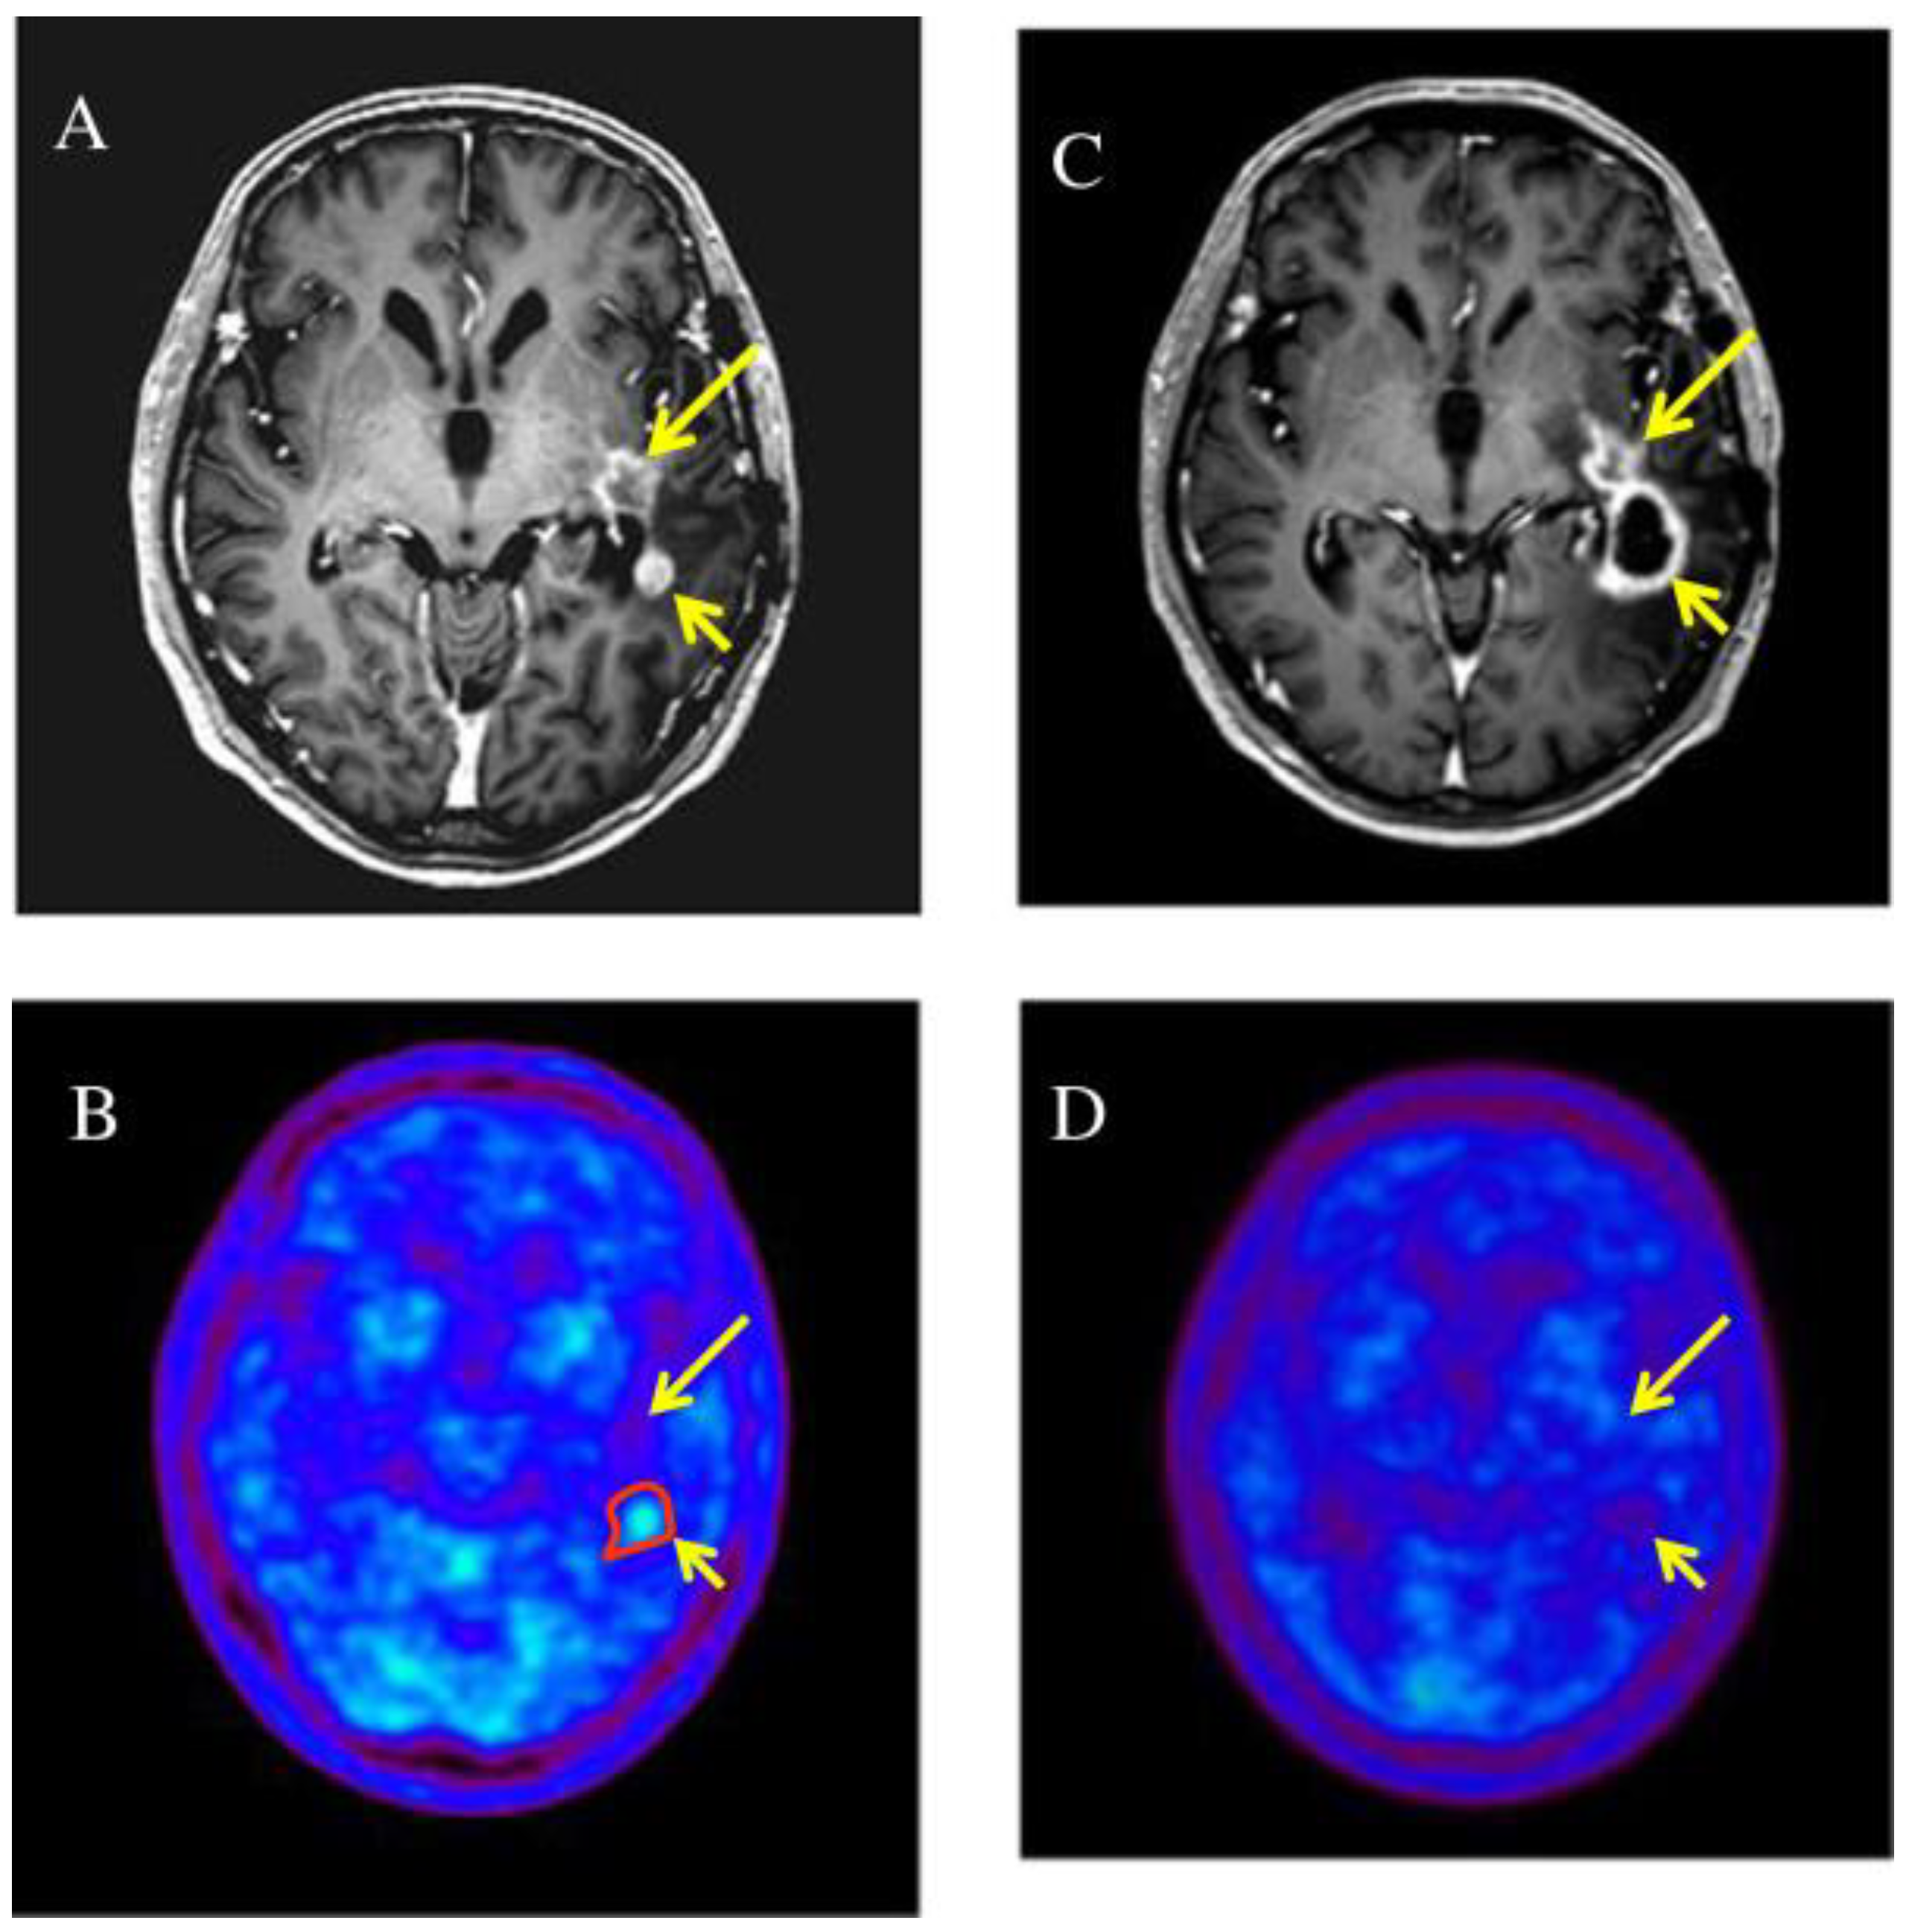

In 2014, Miwa et al. treated 22 patients with relapsed HGG with hypo-fractionated SRT planned with 11C-methionine positron emission tomography (MET-PET)/computed tomography (CT)/magnetic resonance imaging (MRI) fusion (Figure 3). PTV was obtained from GTV, in detail from PET/MR images plus 3 mm margin. The total delivered dose was 25–35 Gy with fractions of 5–7 Gy, respectively. The median overall survival time was 11 months, and the median progression-free survival time was 6 months from the date of re-irradiation, respectively. The OS of patients who received combined TMZ chemotherapy was greater. The authors proved the usefulness and importance of PET in the planning and follow-up of re-RT. They compared MRI and MET-PET images of the relapse and noted that only a part of the lesion that can be seen in MRI had MET high-uptake. The GTV was identified precisely on the MET uptake alone. Five months after the SRT, an MRI was performed, which indicates an increase in the size of the irradiated lesion. The control PET, however, does not show any area of MET high-uptake and is therefore suggestive of pseudoprogression [58].

Figure 3.

Two enhanced lesions (long and short arrow) were demonstrated in the left temporal lobe on T1-weighted magnetic resonance imaging (A), MET-PET demonstrated a MET high-uptake on the region of short arrow (B), only the enhanced lesion (short arrow) was treated with RT; 5 months later it was increased in size (C) but not in uptake (D) (suggestive of pseudoprogression) while the non treated lesion remained stable [58].